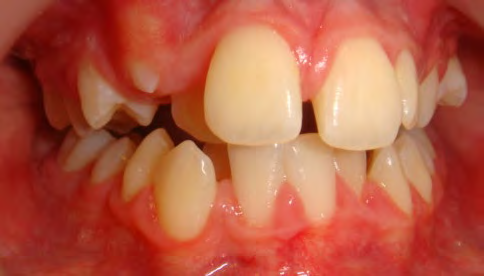

All of the patients below had been told they required extractions by orthodontists, some insisting that they could not be treated without extractions.

They were all treated without extractions, head gear or facemasks at Vakresmil and represent just a small sample of cases treated between 2004–2014.

The patient below had severe crowding of both upper canines and the lower right 5. The upper 4’s and 2’s were actually in contact.

Below are cases treated at Vakresmil without extractions within the last three years. The families had been told, “It is simply not possible for your child to be treated without extractions” by orthodontists. Judge for yourself if that was right or wrong.

The overall aim is to produce the best smile we can — a “beautiful smile”, if you will — without premolar extractions, headgear, facemasks or banded appliances. A smile that both the patient and we at Vakresmil can be proud of.